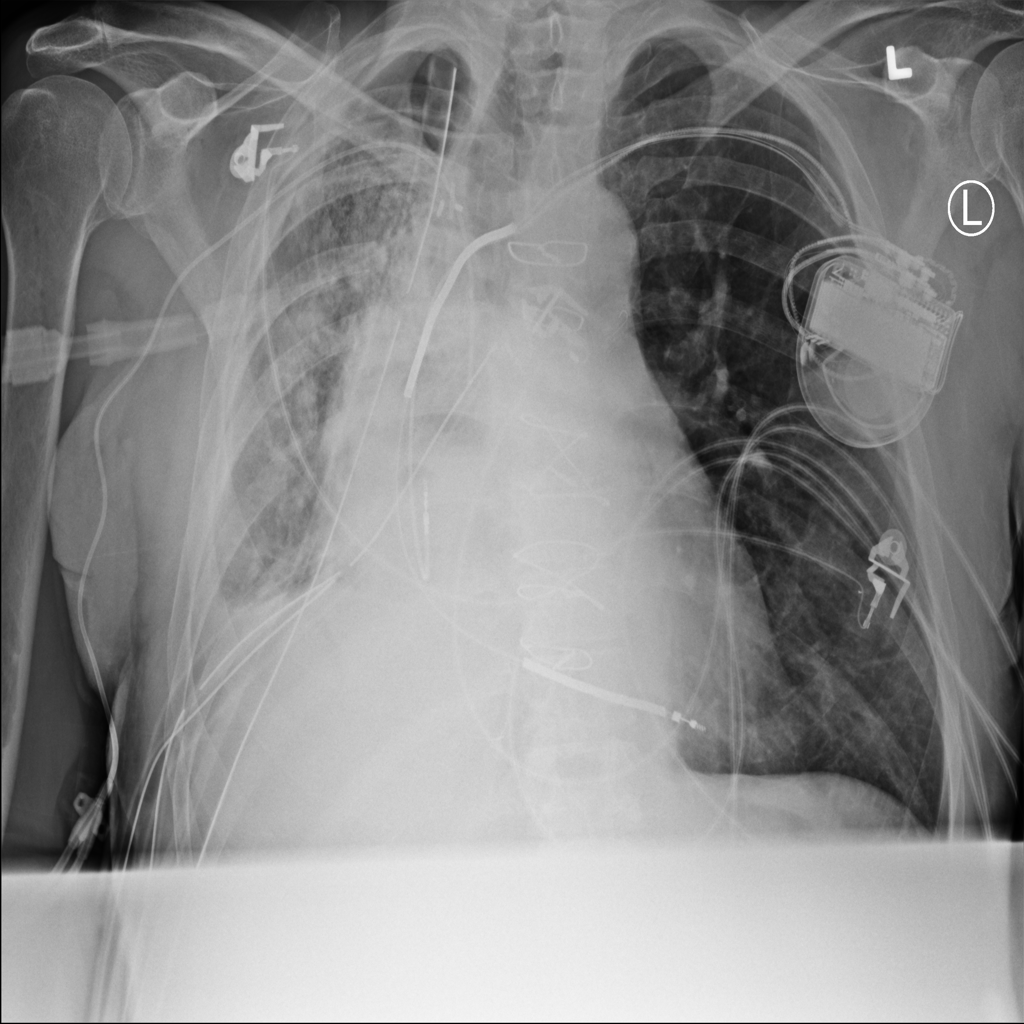

Pneumothorax

Pneumothorax means air is present outside the lung in the pleural space, which can allow part of the lung to collapse. It is an important imaging finding because the size and clinical impact can vary widely.

Showing up to 90 reference images for Pneumothorax.

PAT-4639 · IMG-013Pneumothorax

PAT-4639 · IMG-013

AP